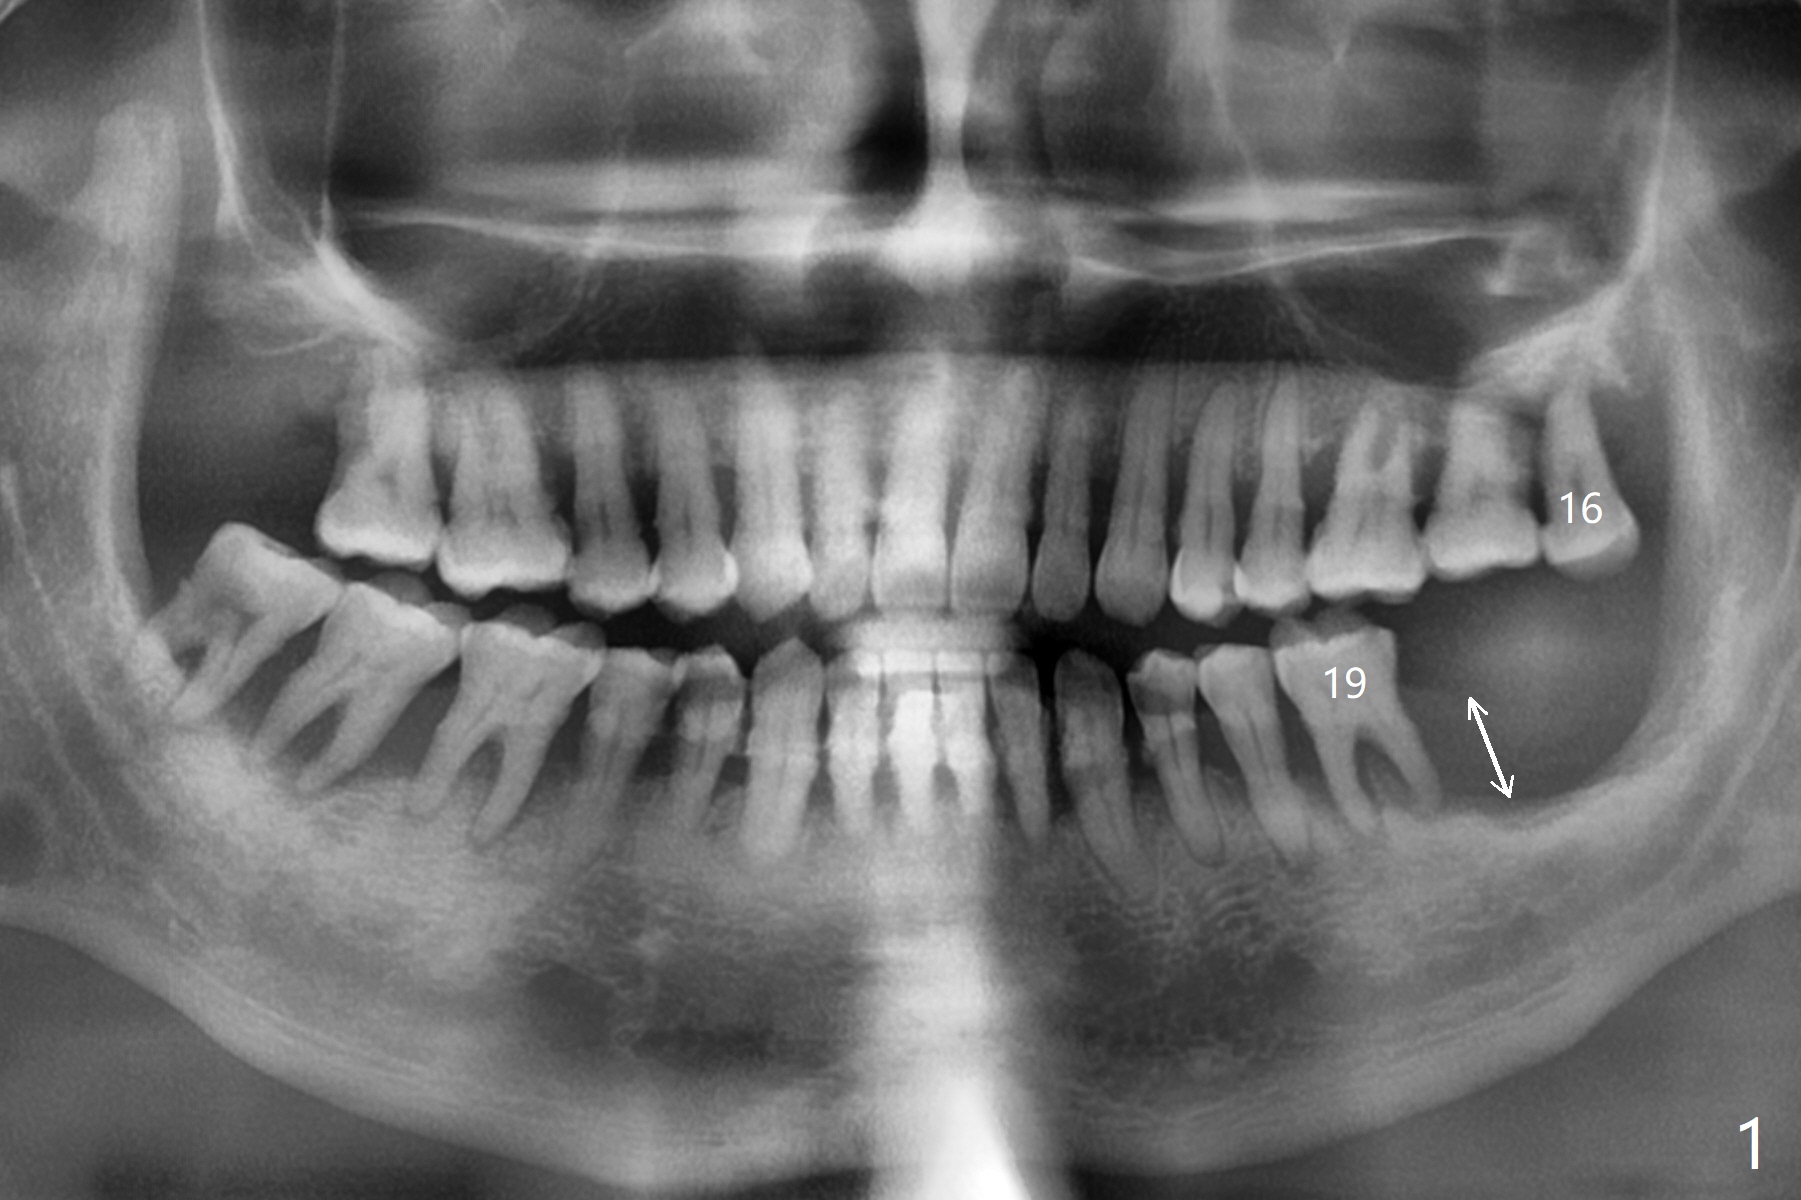

56岁男几十年拒绝牙周炎治疗,也不愿意拔除所有牙齿做全口植牙修复。17,18号牙自行脱落,现在要求拔除16,19;18,19种植(图一),后者牙龈厚(双箭头),但是18号牙骨质高度不足(图二),勉强植入5x7.3毫米植体。15,16骨质吸收严重(图三),16,19拔除,局部深洗后(图四:黑色),为了延长15号牙使用期,16号牙牙槽窝植骨(图五:红色)。19号牙种植徒手,因为邻牙(包括20,21号牙))松动,做导板不准确,钻洞使用环形钻头(图六),保留骨塞(bone plug),用于18号牙骨质高度骨块移植。19号牙拔除后,往远中18牙位做潜行分离(图七:黑色)。19种植(绿色),基台(粉红色),骨粉(圆圈),临时牙冠(白色),16号牙粘性骨粉植骨(红色),PRF,Cytoplast覆盖(白线),缝合。从19号牙钻洞取来的骨塞,塞入18号牙潜行分离处(图八);利用临时牙冠和22号牙以及钢丝,树脂固定20,21号牙(蓝色),并且降低咬合(*)。最后,用螺钉固定骨塞(图九:深蓝色)。